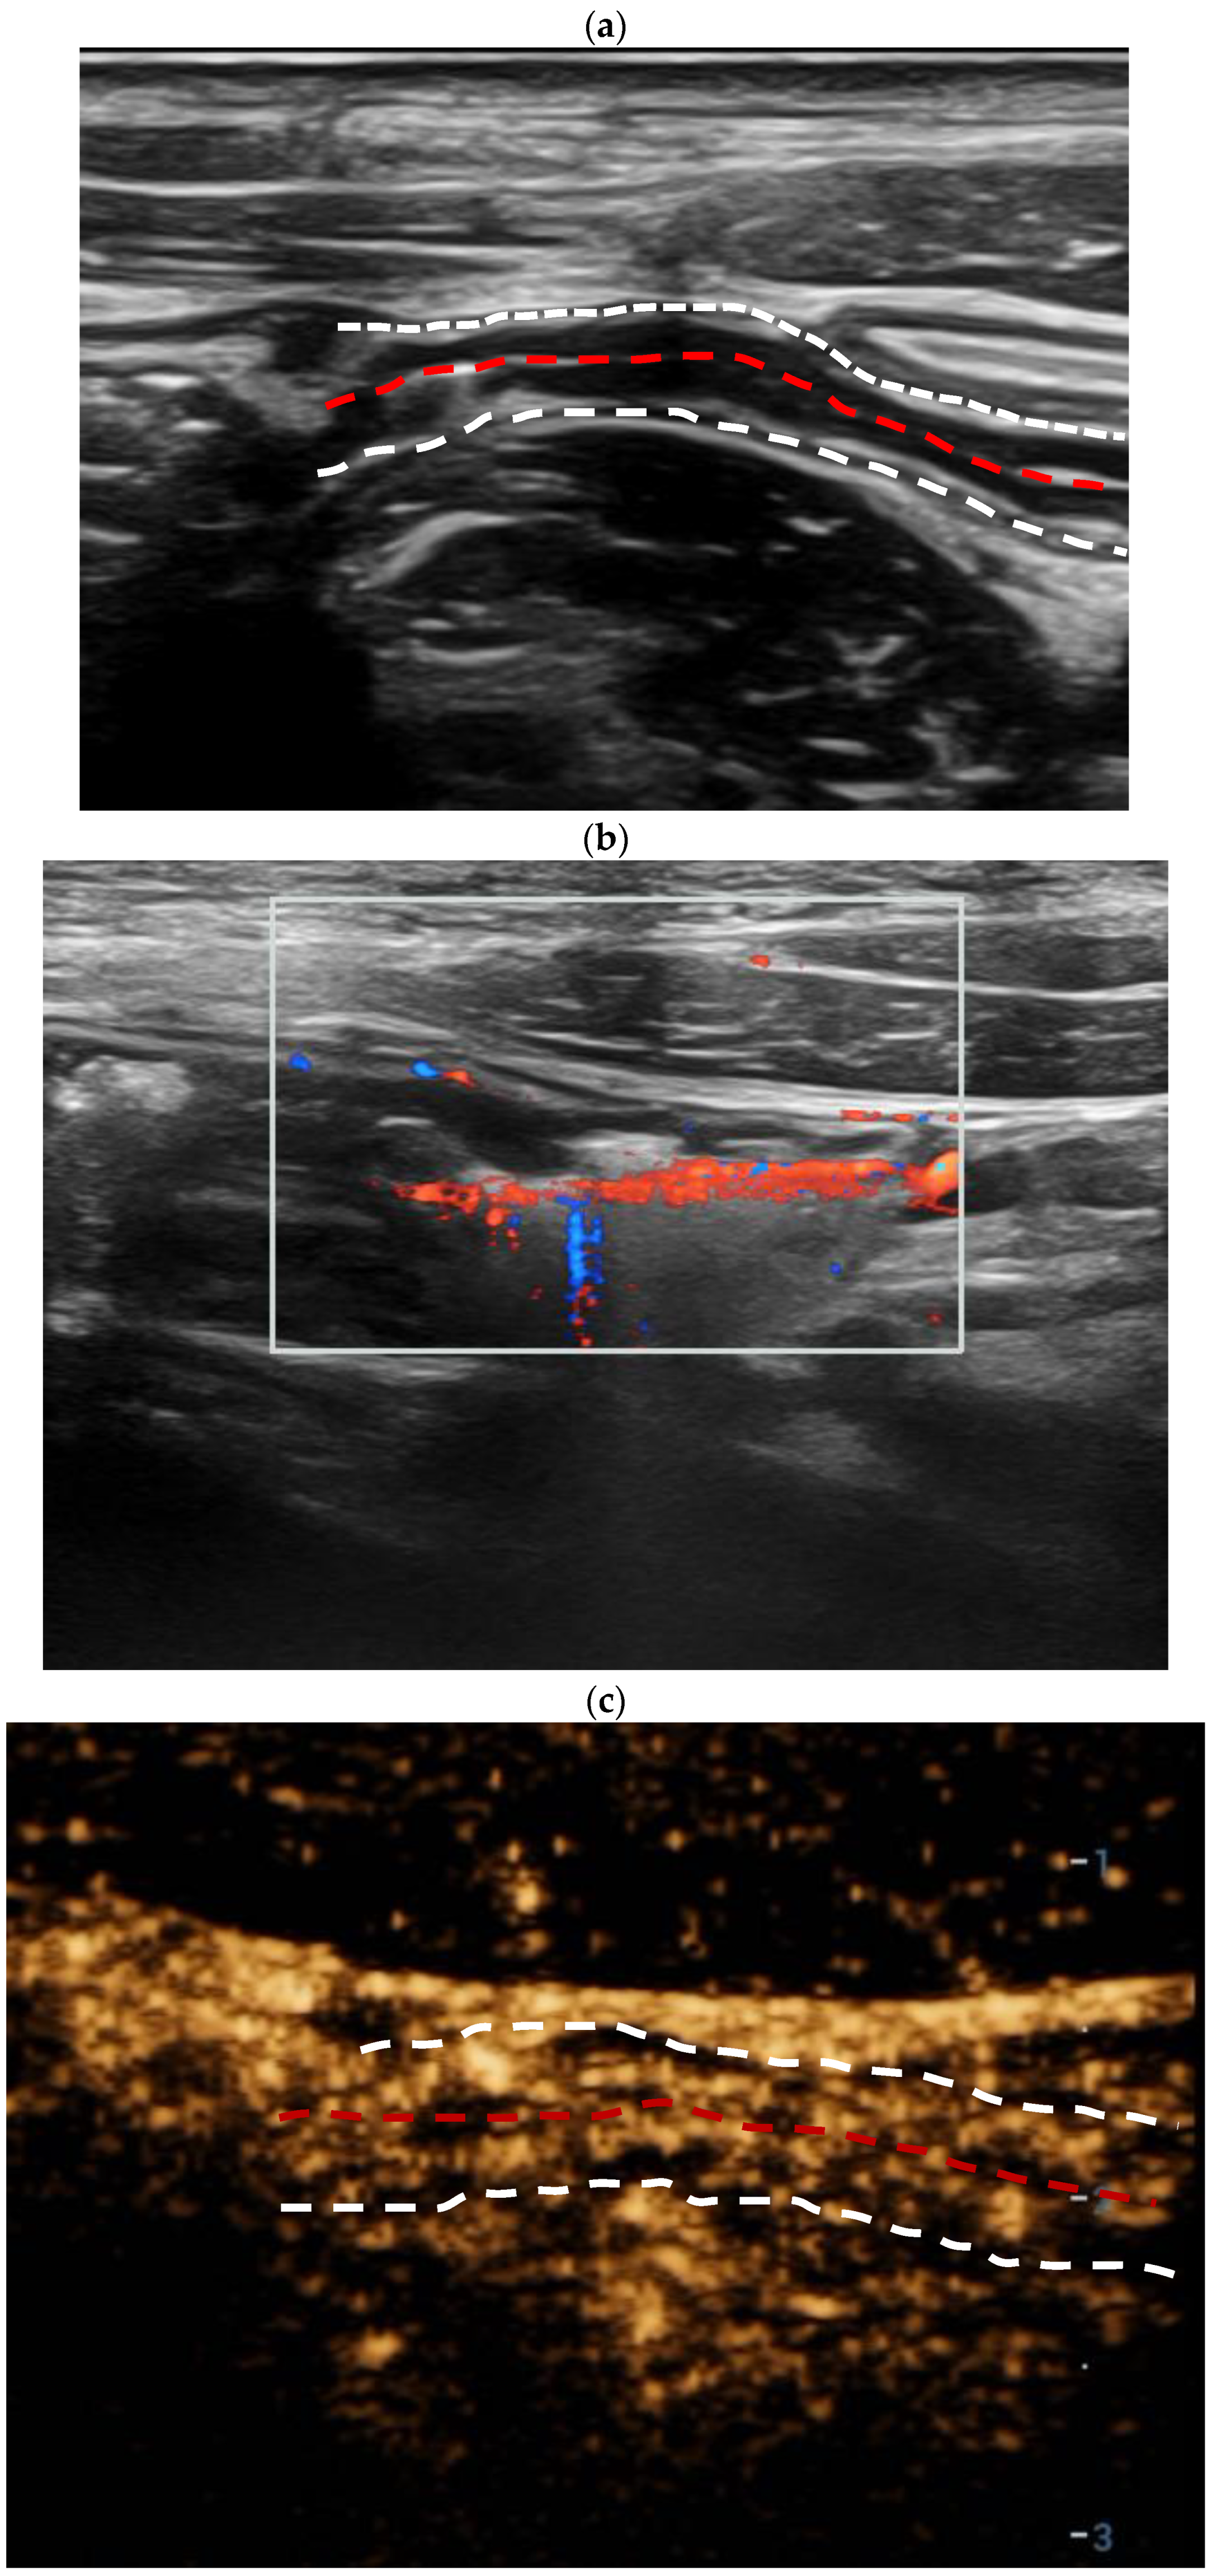

3.2. Intestinal Ultrasound Features

3.3. Dynamic Contrast-Enhanced Ultrasound (DCE-US) Quantitative Analysis

| MFH | |||

| Absent | 12 (30.8%) | 13 (100%) | <0.001 * |

| Present | 27 (69.2%) | 0 | |

| CEUS enhancement | <0.001 * | ||

| Pattern I | 24 (61.5%) | 1 (7.7%) | |

| Pattern II | 10 (25.6%) | 3 (23.1%) | |

| Pattern III | 5 (12.8%) | 8 (61.5%) | |

| Pattern IV | 0 | 1 (7.7%) | |